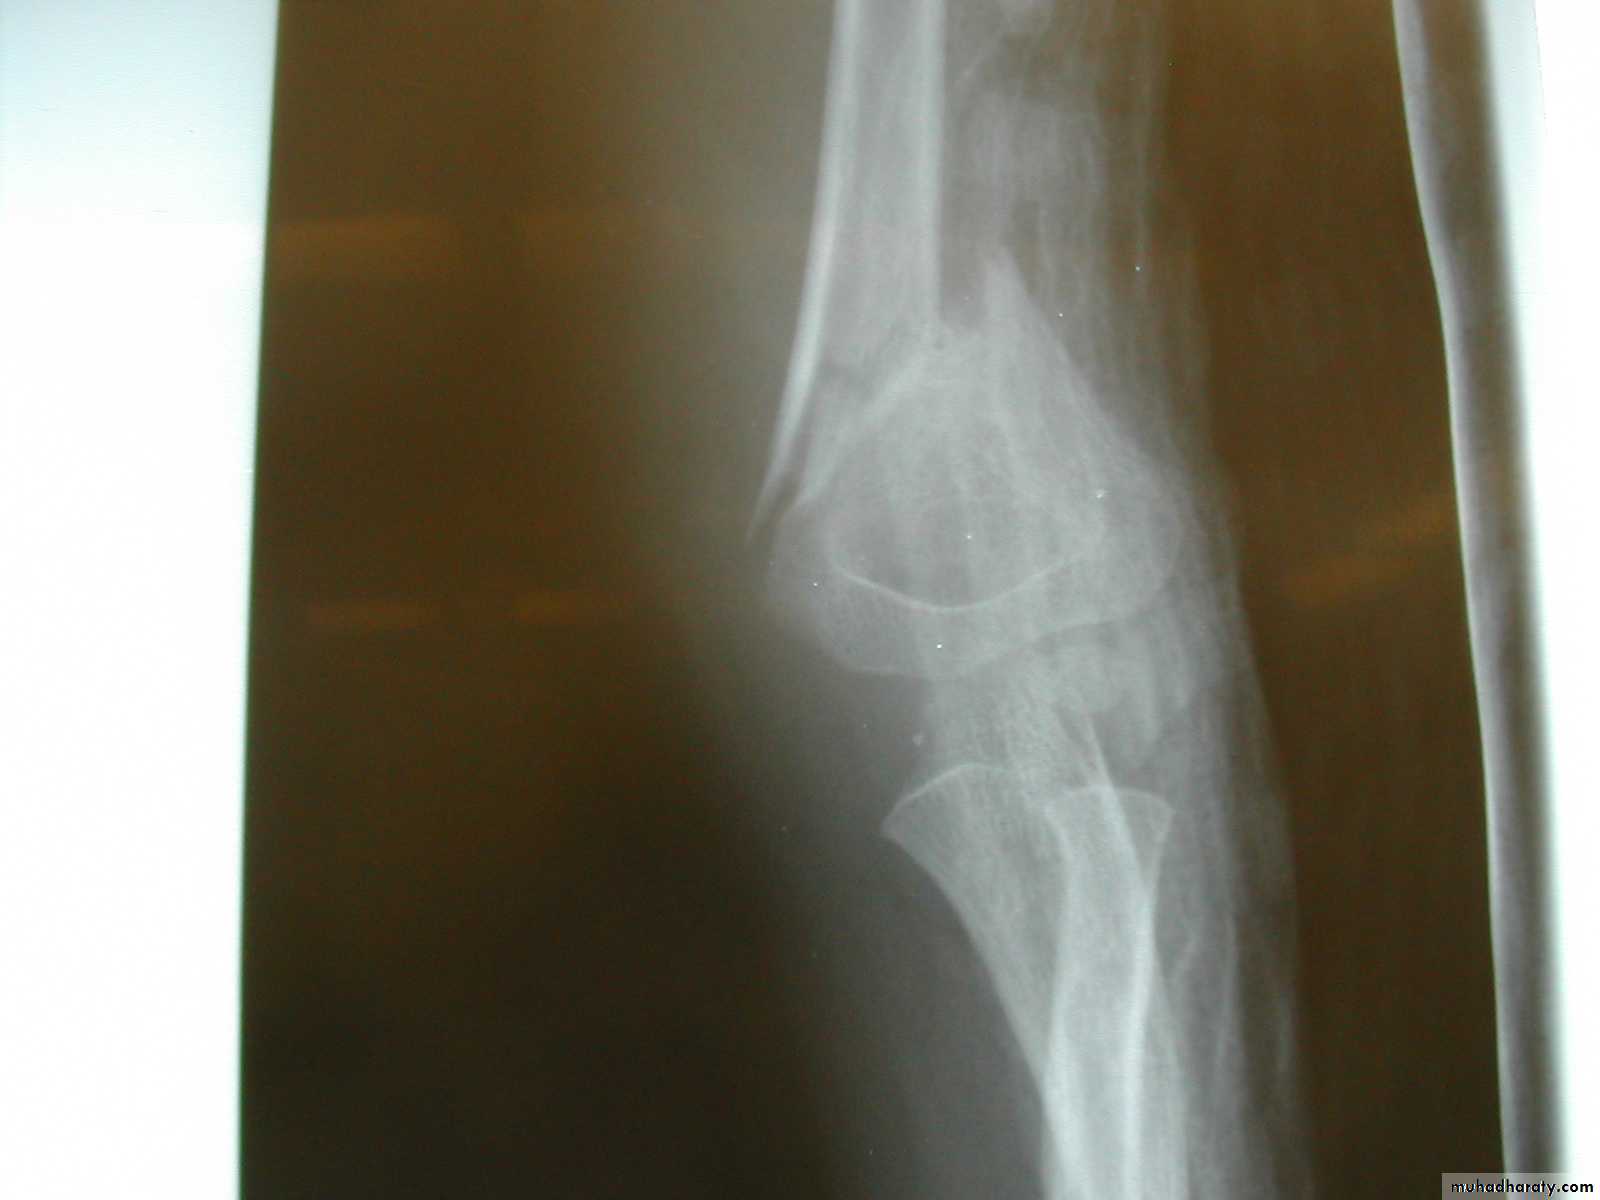

Five y.o. male with this fracture pattern

• Following obtaining a satisfactory closed reduction how do you propose to stabilize it?Multiple lateral pins

Stable ??Five y.o. male with this fracture pattern

• Following obtaining a satisfactory closed reduction how do you propose to stabilize it?

Medial-lateral

retrograde cross pinsDifficult and unstable